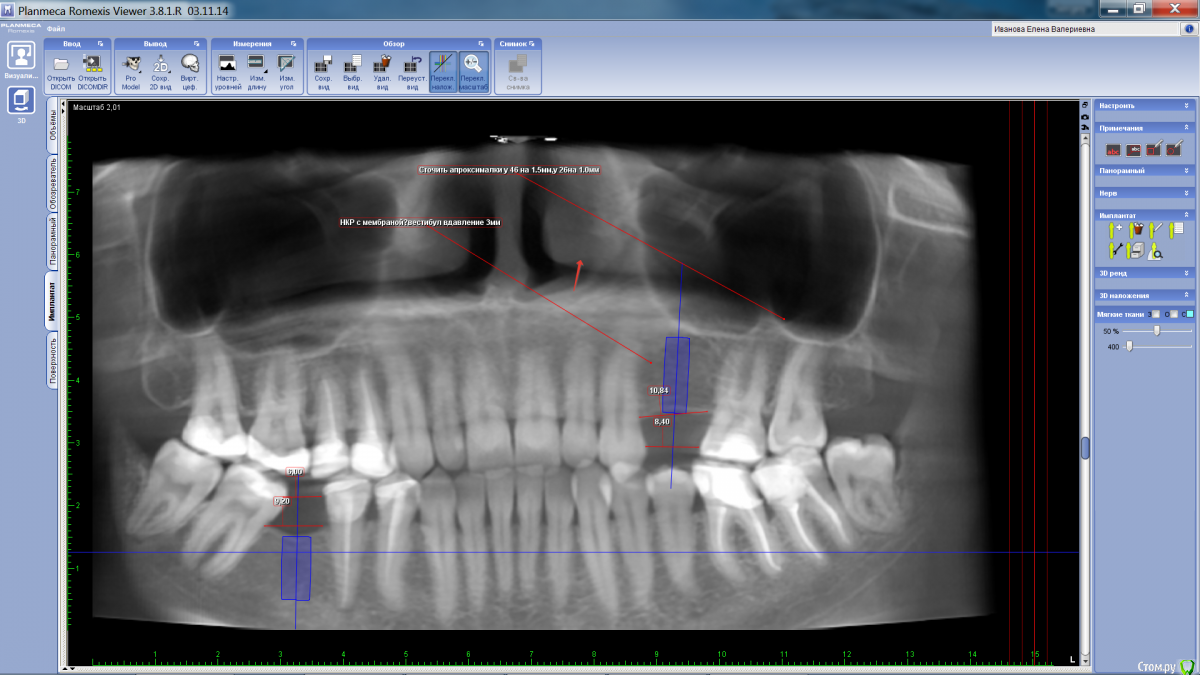

Sergiosse Опубликовано 30 августа, 2015 Поделиться Опубликовано 30 августа, 2015 (изменено) Подскажите начинающему доктору тактику.Планируется установка импланта 4.5Х12мм, в обл.24 зуба. Вестибулярно кость атрофирована по высоте и ширине.Проводить ли имплантацию одномоментно с НКР cera os+ аутокость , сверху мембрана.Делаю первый раз, на что обратить внимание? Заранее благодарен за советы. Ширина гребня 3,7 мм. Изменено 30 августа, 2015 пользователем Sergiosse Ссылка на комментарий

Doctorstomlis Опубликовано 30 августа, 2015 Поделиться Опубликовано 30 августа, 2015 Там вроде бы нет двух зубов?24 и 25?Коронка потом будет шириной 8,4мм?Практически моляр вместо двух премоляров? Ссылка на комментарий

Sergiosse Опубликовано 30 августа, 2015 Автор Поделиться Опубликовано 30 августа, 2015 Сколько ширина альвеолярного гребня?Видна только высота в срезе.3,7 мм. Ссылка на комментарий

Sergiosse Опубликовано 30 августа, 2015 Автор Поделиться Опубликовано 30 августа, 2015 (изменено) Я бы тут кость не добавлял вообще, только десну вестибулярное вдавление порядка 3 - 3.5 мм, если поставлю импл. в идеальную позицию, полагаю будут оголены все витки резьбы спереди. Какой толщины добавлять кость, с рассчетом на усадку? Изменено 30 августа, 2015 пользователем Sergiosse Ссылка на комментарий

major Опубликовано 2 сентября, 2015 Поделиться Опубликовано 2 сентября, 2015 Там вроде бы нет двух зубов?24 и 25?Коронка потом будет шириной 8,4мм?Практически моляр вместо двух премоляров?Вопрос без ответа. Может быть с ортопедом еще раз подумать над окклюзионной схемой(дистализировать моляры, дать место еще одному премоляру)? Просьба к опытным коллегам прокрутить варианты, на будущее))) Ссылка на комментарий